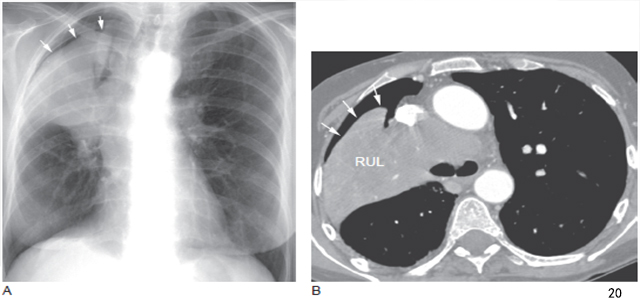

2、外部性气胸

平片或CT 扫描显示了新月形气体聚集在不张肺叶周围胸腔(图20)。最常见于右上叶肿瘤。

图20 小细胞肺癌的阻塞性肺不张后外部性气胸,右肺上叶支气管阻塞

A. 胸片显示右肺门肿块和右上叶不张伴肺尖气胸( 箭头);B.CT 显示气胸(箭头) 包绕右上叶不张, 可见右上叶支气管阻塞,为典型的外部性气胸表现